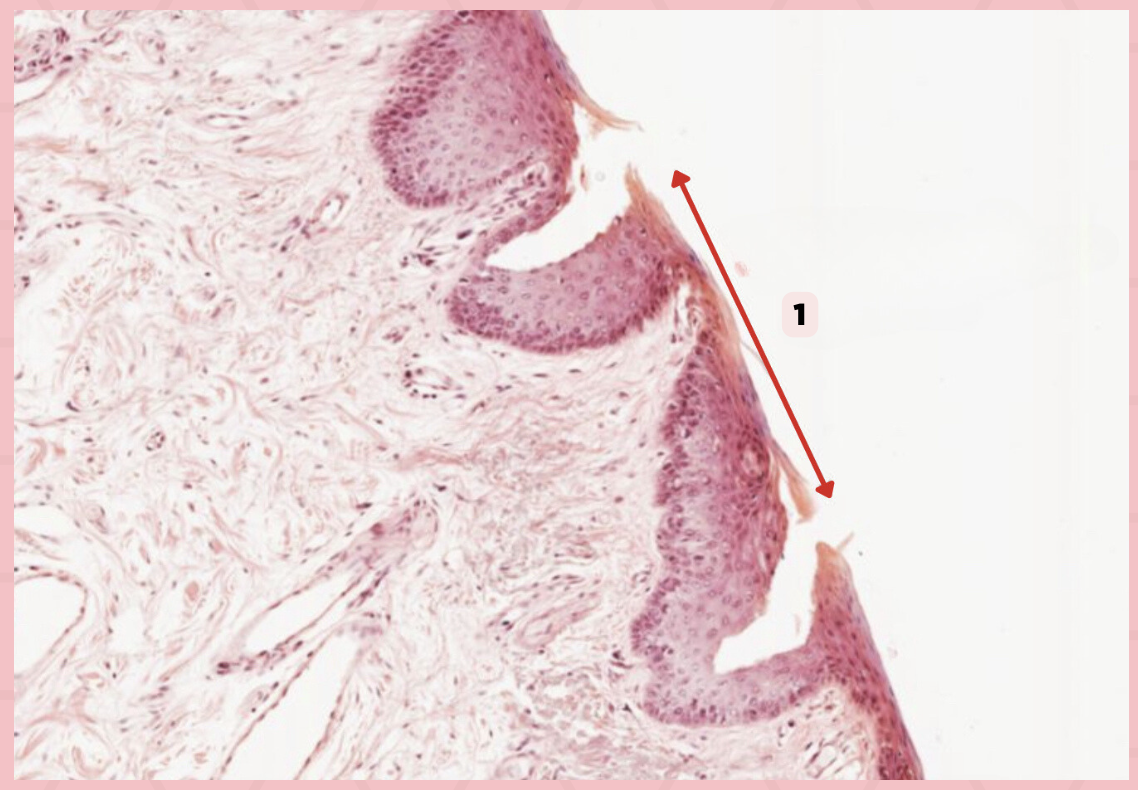

d. Mucosa/Mucous Membrane

Identify the structure labelled in the given image?

a. Epidermis

b. Dermis

c. Hypodermis

d. Mucosa/Mucous Membrane

b. Nonkeratinized stratified squamous epithelium

Identify the structure’s lining epithelium given in the image?

a. Keratinized stratified squamous epithelium

b. Nonkeratinized stratified squamous epithelium

Lip

What specimen is being showed in the picture?

Non-Keratinized Stratified Squamous Epithelium (Mucosa/Mucous Membrane)

Identify the structure labeled as 1.